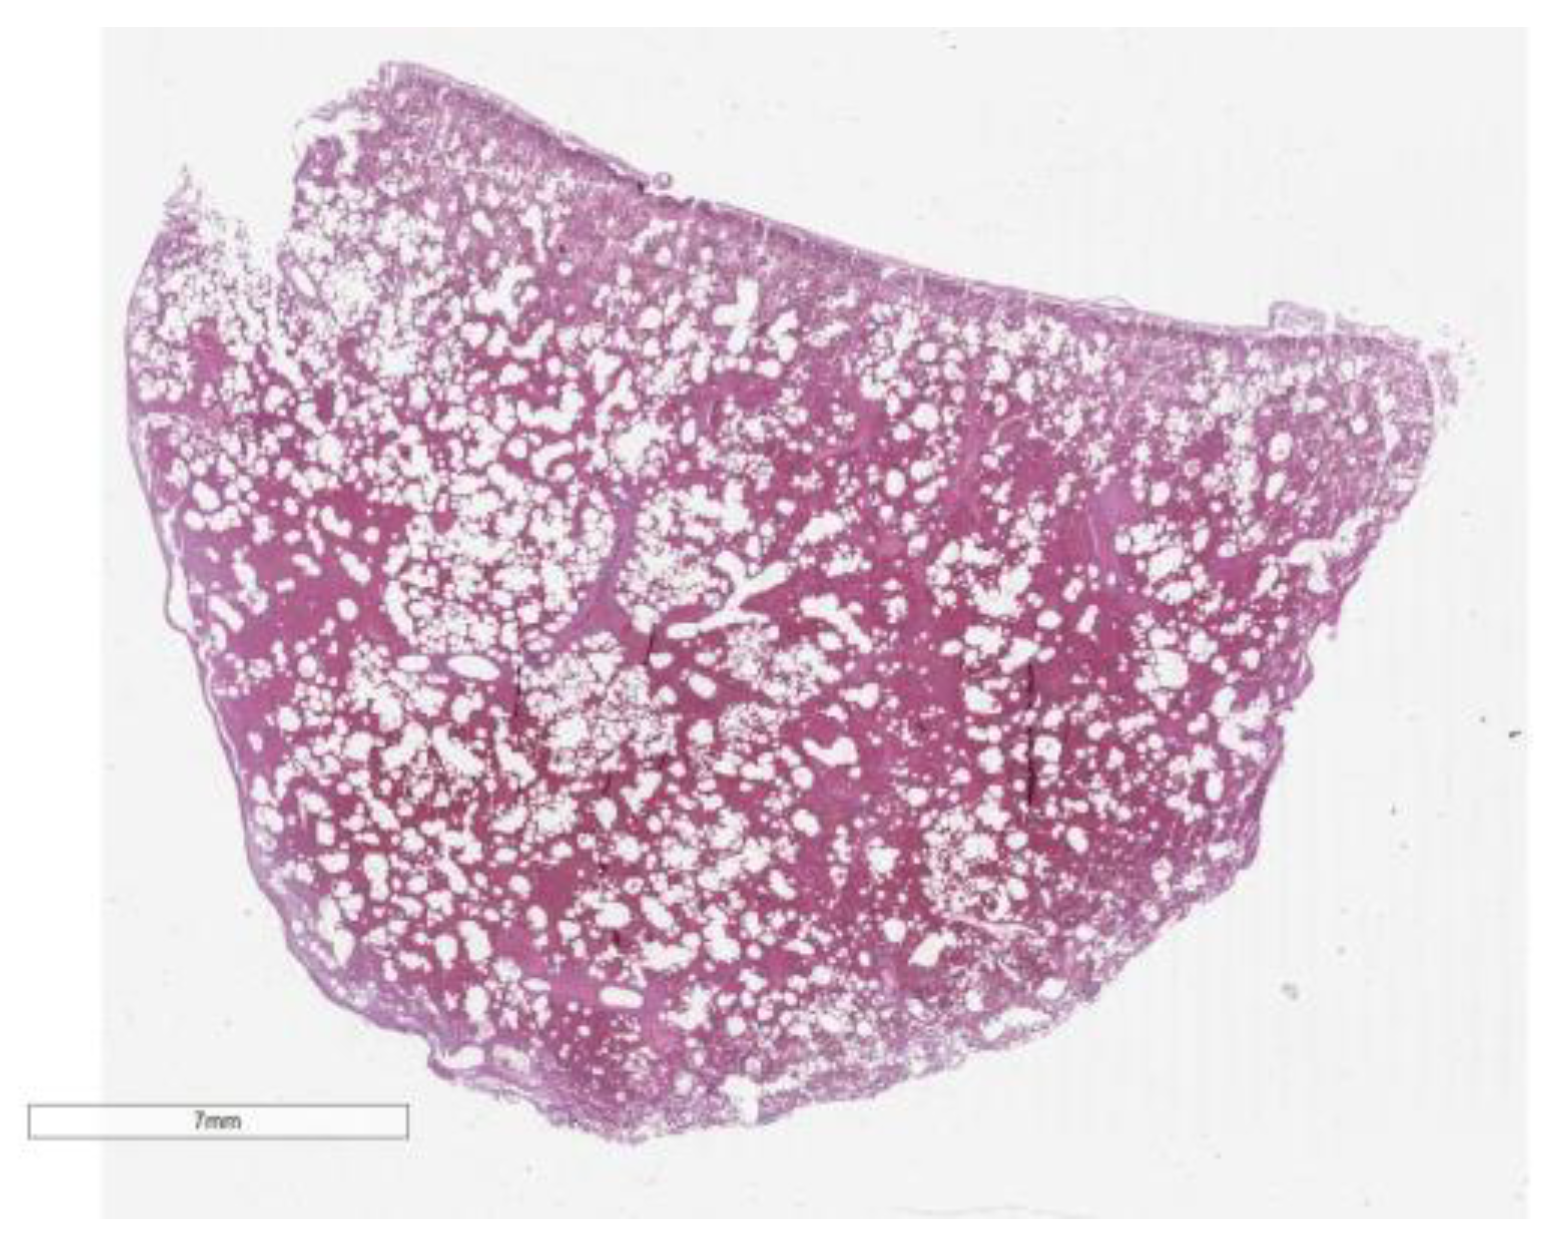

Furthermore, the liver was affected by chronic lymphocytic portitis, highlighting an inflammatory response within the portal areas. At the pulmonary level, the findings were particularly severe, with widespread pulmonary hemorrhage and areas of edema. Additionally, emphysematous changes were noted, suggesting alterations in lung tissue structure and function. These comprehensive histological findings underscore the multi-organ impact of the underlying disease processes, contributing to a complex clinical presentation. (Figure 3 and Figure 4).

Figure 3. Section in H&E that show the hemorragie end the alveolar damn.

Figure 4. Section in H&E (x20) that focus on alveolar damn, and also show the hemorragie an the infiltrate.